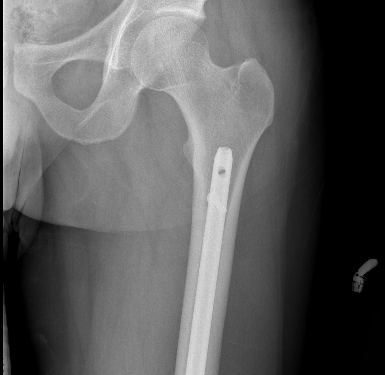

1. Retrograde nail

Nail

Iannacone et al J Orthop Trauma 1994

- 41 distal femur fractures treated with retrograde nail

- 4 non unions requiring revision fixation

- 4 fatigue fractures of the IMN; changed to using minimum 12 and 13 mm rods

Retrograde Nail

Surgical Technique